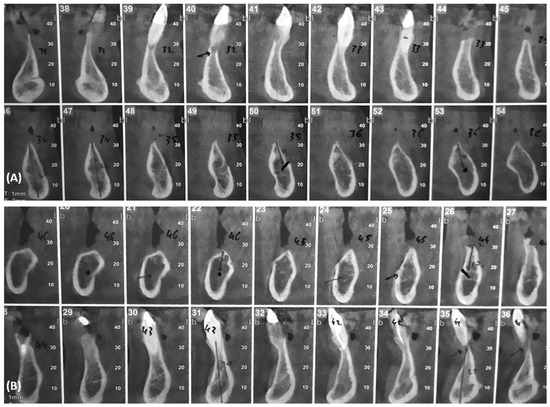

2. Case Report

Surgery Appointment